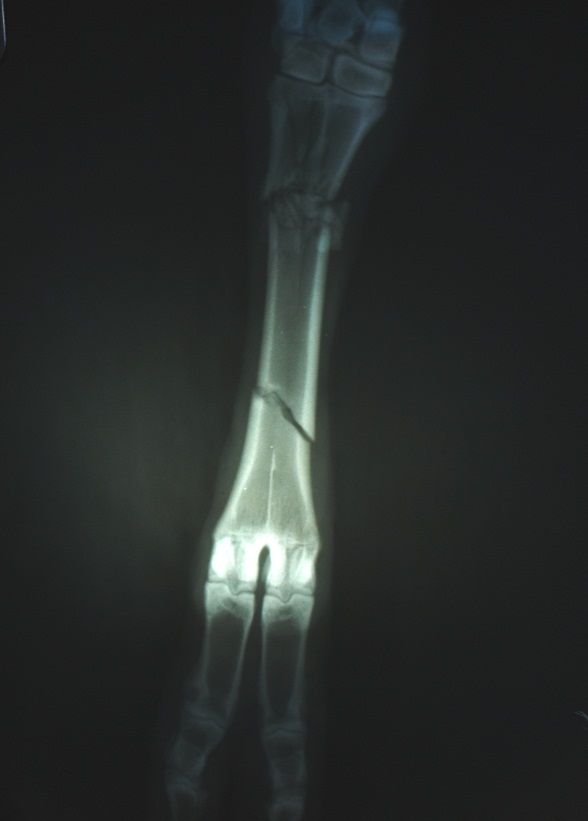

Использование аппарата наружной фиксации при лечении перелома у овцы

сразу после перелома